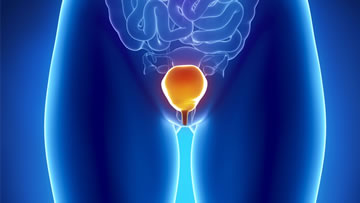

• Enfermedades de las vías urinarias, (infecciones, incontinencia urinaria, hipertrofia prostática)